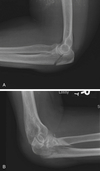

Describe this fracture?

MONTEGGIA - Fracture of junction of proximal & middle thirds of ulna w/ anterior dislocation of radial head - PIN injury (weak thumb or finger ext) - FOOSH with forced pronation or direct blow to ulna - Cast in supination in KIDS